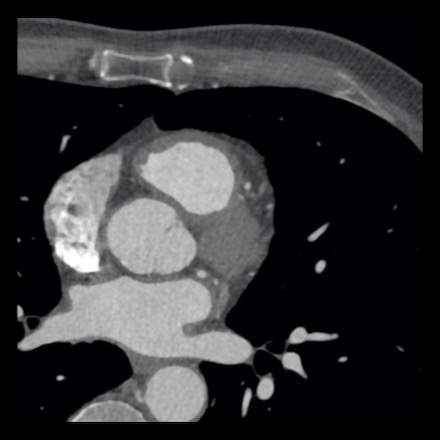

case 1 – CAD-RADS 2/P1

First, scroll through the scan.

Not all images are included. Some images without any abnormalities are skipped

from the series.

How would you describe the findings on the coronary CTA?

The findings are:

- Agatston score of

this patient was 14 (P1). Please, also note the calcification of the aortic valve. - Some partially

calcified and calcified plaques are present in the LAD with mild stenosis

(25-49%). - Calcified-plaque in

the LCX causing minimal stenosis (<25%). - Non-calcified

plaque in the distal RCA causing minimal stenosis (<25%). - This patient classifies

as CAD-RADS 2/P1, which means no further workup is needed.